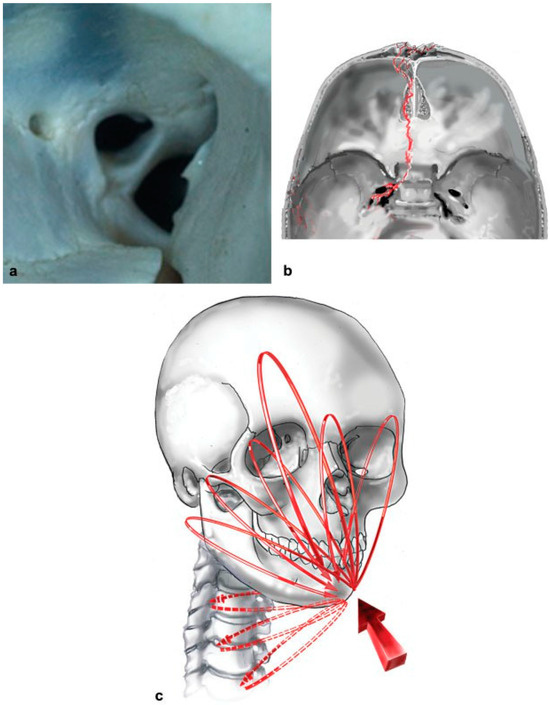

- Pollock, R.A. (Ed.) Buttresses of the craniomaxillofacial skeleton. In Craniomaxillofacial Buttresses: Anatomy and Operative Repair; Thieme: New York, NY, USA, 2012. [Google Scholar]

- Pollock, R.A. Current principles of repair. In Craniomaxillofacial Buttresses: Anatomy and Operative Repair; Pollock, R.A., Ed.; Thieme: New York, NY, USA, 2012; pp. 29–46. [Google Scholar]

- Pollock, R.A. (Ed.) Pancraniomaxillofacial injury. In Craniomaxillofacial Buttresses: Anatomy and Operative Repair; Thieme: New York, NY, USA, 2012; pp. 194–207. [Google Scholar]